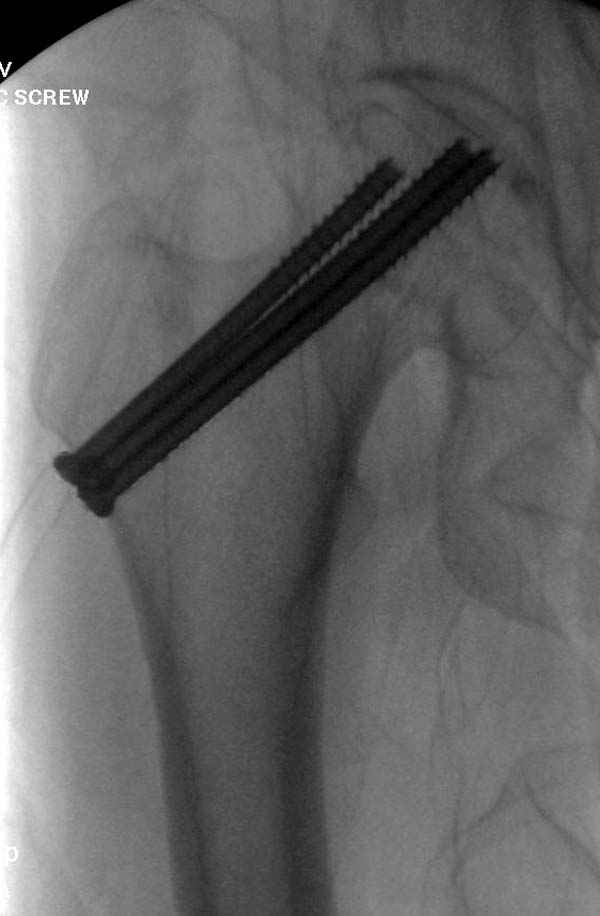

На второй день после выписки упал дома. Снимки приложены. Коллеги рекомендуют удаление шурупа и вытяжение. Что делать?

Привет из солнечного Будапешта с Eurotrauma-2008. Да, замечательный пример. Получается, профилактику расхождения отломков шейки надо было проводить каким-то реконструкционным или проксимальным гвоздем, причем сразу длинной версией. Сейчас, наверно, так и надо бы сделать.

Убрать винты, каким-то джойстиком в вертельной области сделать репозицию шейки, фиксировать ее спицами, а дальше вправлять и фиксировать как вертельный перелом.

Правильно, ситуация изменилась, как говорят у нас теперь "different animal", надо решать проблему подвертельного перелома. При наличии различных вариантов фиксаторов, включая Страйкер Гамма 3, мы выбрали DePuy Antegrade Trachanteric Nail из-за многовариантности проксимальной фиксации и двойного изгиба. Вводится через вертел под 8 градусным углом, и есть достаточный передний диафизарный изгиб, предупреждающий пенетрацию дистального переднего кортекса.